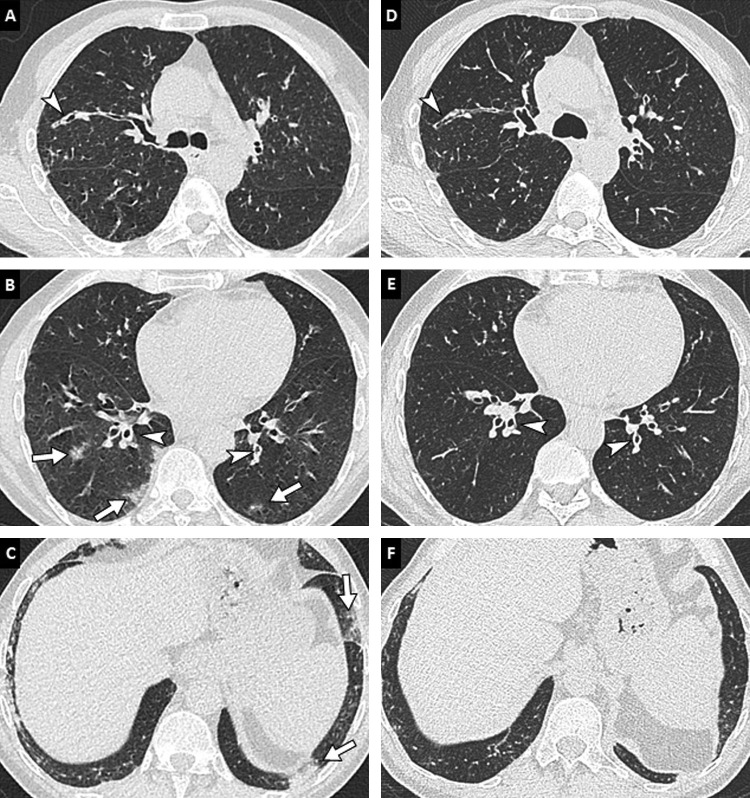

Fig. 4.

78-year-old woman with COVID-19 pneumonia. (A, B) Initial unenhanced chest CT image in the axial plane (lung window: W1600/L-500 HU) shows bilateral and peripheral areas of ground-glass and consolidation. (C, D) Follow-up contrast-enhanced CT images performed 13 days later to rule out pulmonary embolism reveal progression in extent and in density of pulmonary lesions with a crazy paving pattern (white arrowheads) and consolidation areas (arrows). (E, F) Contrast-enhanced CT images obtained 28 days after the onset of symptoms show partial regression of consolidation areas but persistence of fibrotic streaks (black arrowheads) with architectural distortion.

The total extent of lung involvement on the first CT examination correlates with clinical severity [13], [25], [30]. The French Society of Thoracic Imaging (SIT) recommends grading lung involvement as absent or minimal (< 10%), moderate (10–25%), extensive (25–50%), severe (50–75%) or critical (> 75%) (Fig. 5 ). The density of pulmonary lesions is also a marker of severity, since lung consolidation areas appear more extensive than ground-glass opacities in critically ill patients [30]. Pleural effusion and early architectural distortion with traction bronchiectasis on initial chest CT would also indicate a poor prognosis [15]. A Chinese series suggests that consolidation in upper lobes on initial CT is also associated with poor outcomes [31].

Fig. 5.

Various degrees of lung involvement in COVID-19 pneumonia in four different patients. Unenhanced CT images of the chest (lung window: W 1600/L–500 HU) in the axial (up) and coronal (down) planes show typical examples of moderate (< 25%), extensive (25–50%), severe (50–75%) and critical (> 75%) lung involvement (A, B, C, D, respectively). The latter images are (D) characteristic of acute respiratory distress syndrome with a gravitationally dependent gradient.